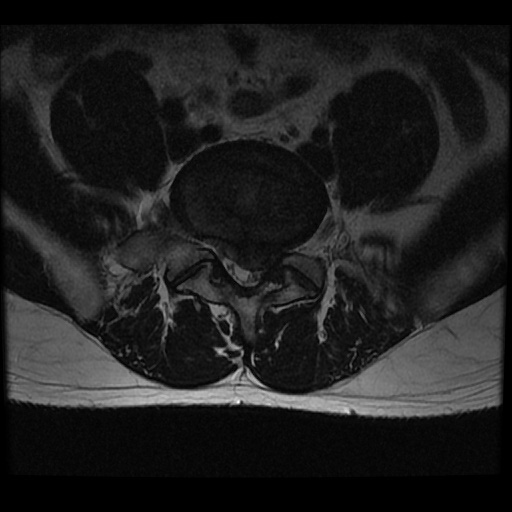

디스크 환자분들이 대체 왜 본인이 협착증이라고 오해하시는 걸까요? 그 이유는 첫 번째, 의사에게 ‘협착’이라는 단어를 들었기 때문입니다. 한 10년 전만 해도 안 그랬는데, 최근 허리디스크 환자의 MRI 사진을 보고 환자의 척추관이 ‘협착되었다’라고 표현하는 의사들이 점점 많아지고 있습니다. ‘협착’의 사전적 의미는 ‘어떤 관이나 구멍의 안쪽 폭이 좁아진 상태’를 말합니다. 물론 허리디스크도 디스크의 수핵이 밀려나오기 때문에 척추관의 공간이 좁아지긴 합니다. 그러나 이것은 엄밀한 의미의 협착증은 아니며, 이것을 ‘협착’이라고 표현하는 것도 바람직하지 않습니다. ‘협착’이라는 말을 들은 환자들이 ‘협착되었다고? 아, 내가 척추관협착증이구나’라는 오해를 할 수 있기 때문입니다.

다음으로 협착증이라고 오해하는 이유 두 번째, 환자 본인이 디스크의 높이가 낮아진 걸 보고 협착증이라고 오해하기 때문입니다. 허리디스크가 퇴행되거나 탈출되면 수핵이 말라 없어지거나 빠져나가고, 이에 따라 디스크의 높이가 많이 낮아집니다. 그러면 환자들이 본인의 MRI 에서 디스크의 높이가 낮아진 것을 보고, ‘이게 협착된 거구나’라고 오해를 하게 되는 것입니다. 하지만 이는 그냥 디스크가 낮아진 거지 협착증이 아닙니다.

진짜 협착증은 ‘간헐적 신경성 파행 증상’이 꼭 나타나야 합니다. 허리협착증 환자들은 걸으면 다리에 통증이 나타나고 저리거나 힘이 빠지는 등 불편하다가, 앉아서 쉬면 다시 좋아지는 경향이 있습니다. MRI 상으로 척추관이 좁아진 것이 보임과 동시에 반드시 간헐적 신경성 파행 증상까지 나타나야 진정한 의미의 협착증이라고 할 수 있습니다. 이에 반해 허리디스크는 앉아있으면 불편하고, 일어서서 걸으면 통증이 줄어드는 경향이 있습니다. 또, 허리협착증은 보통 몸을 앞으로 숙이면 편하고, 뒤로 젖히면 불편한 증상이 나타납니다. 반면 허리디스크는 앞으로 숙이면 통증이 더 심해지는 경향이 있습니다. 그래서 협착증 환자한테는 허리를 뒤로 젖히는 맥켄지 운동을 절대 하지 말라고 합니다. 하지만 디스크환자는 무리하지 않는 선에서 맥켄지 운동을 해 주면, 통증을 완화하는 데 좋은 효과를 볼 수 있습니다. 가끔 “나는 협착증이었는데 맥켄지 운동을 열심히 해서 나았다.” 이렇게 말하는 환자분들이 있는데, 이분들은 협착증이 아니라 디스크였을 가능성이 높습니다.

허리디스크, 척추관협착증 MRI만 보고 진단하면 안 되는 이유